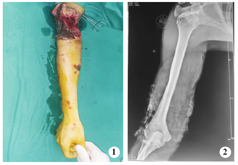

患者 男,25岁,因传送机皮带绞伤致右臂出血、软组织缺损伴血运障碍3 h于2020年8月入太原长城骨伤手外科医院创伤骨科治疗。患者既往体健,无特殊不良嗜好。入院查体:一般情况好,血液动力学稳定。右臂中、下段可见宽约4.0 cm环形软组织缺损,周围组织污染严重,仅肱骨干及后内侧部分肱三头肌相连,残留软组织严重污染。肘部及前臂软组织有明显挤压伤,右肘关节及手部各关节主动伸、屈活动障碍,肢体远端色苍白,皮温低,弹性差,桡、尺动脉不能扪及(图1)。X线片示:右肱骨骨质未见骨折,肱骨远端软组织缺损及异物污染影(图2)。初步诊断:右臂不完全性离断(无骨折)。